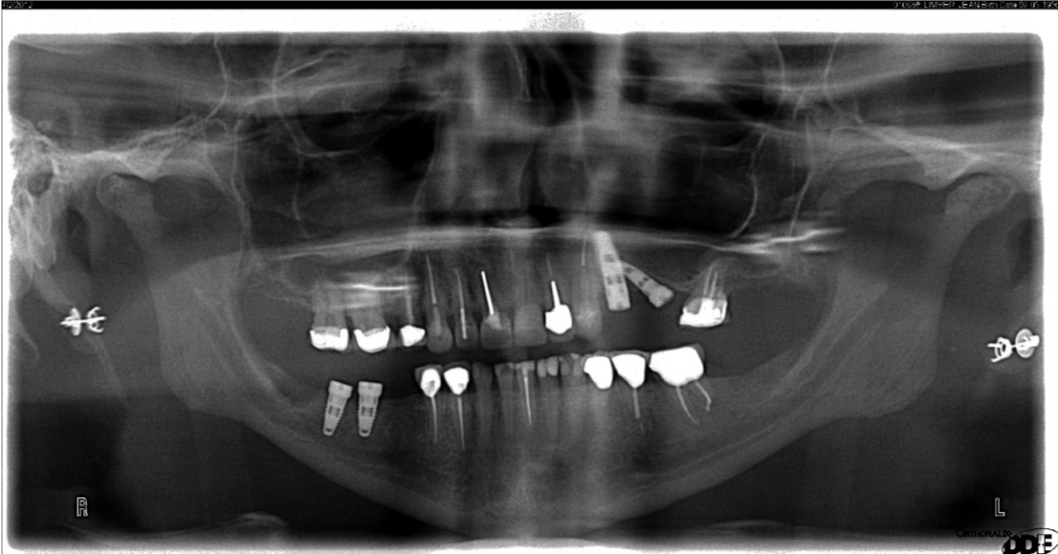

The panoramic radiograph is a good diagnostic tool to implement as well, but with rotation of the cone around the patient's head and neck, there is going to be a distorted bone level. Figure 7 shows an artifact that can occur with the panoramic radiograph, where the patient's earrings relay across the ridge. Artifacts such as this and other distorted findings indicate that the radiograph should not be the sole tool for implant placement.

Fig 7. A panoramic radiograph is an effective diagnostic tool; however, distortions occur, and artifacts may appear.

Figure 7